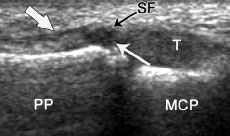

In assessing the “Skiers’s Thumb” injury your Hand Therapist, Physiotherapist or Occupational Therapist at Action Rehab will have a careful look at your ultrasound and x-ray and if you don’t already have an x-ray or ultrasound your therapist might refer you for one. The Hand Therapist at Action Rehab will also physically examine the joint that is injured to assess the severity of the tear and loss of function. Many times the mechanism of injury (how you hurt it) is very useful in diagnosing a Skier’s Thumb injury so the Hand Therapist at Action Rehab will be sure to always ask “how did this happen?”